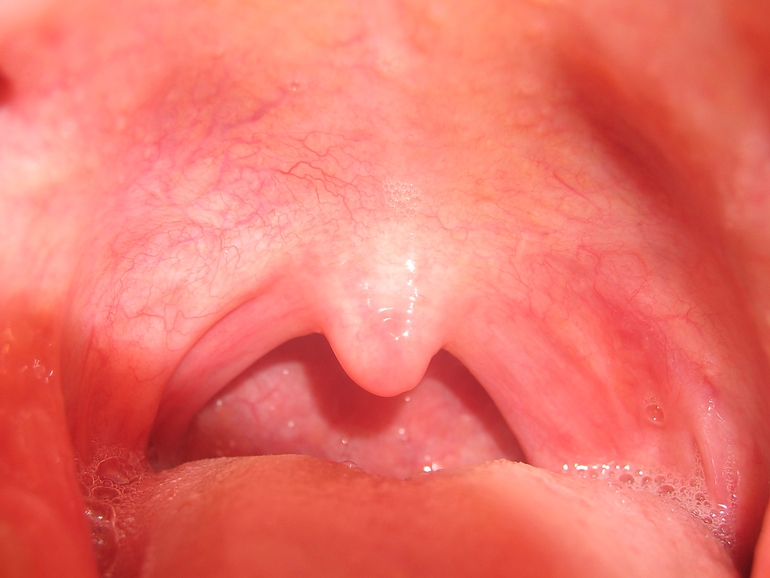

При внешнем осмотре ротовой полости можно заметить небольшую припухлость и резкую гиперемию тканей. Пальпация шейных лимфатических узлов показывает их увеличение и болезненность.

При ангине помимо выше перечисленной симптоматики у ребенка в горлышке можно обнаружить белый налет на миндалинах, язык при этом покрывается серым или желтоватым цветом, температура тела резко повышается до 39 – 40 градусов.